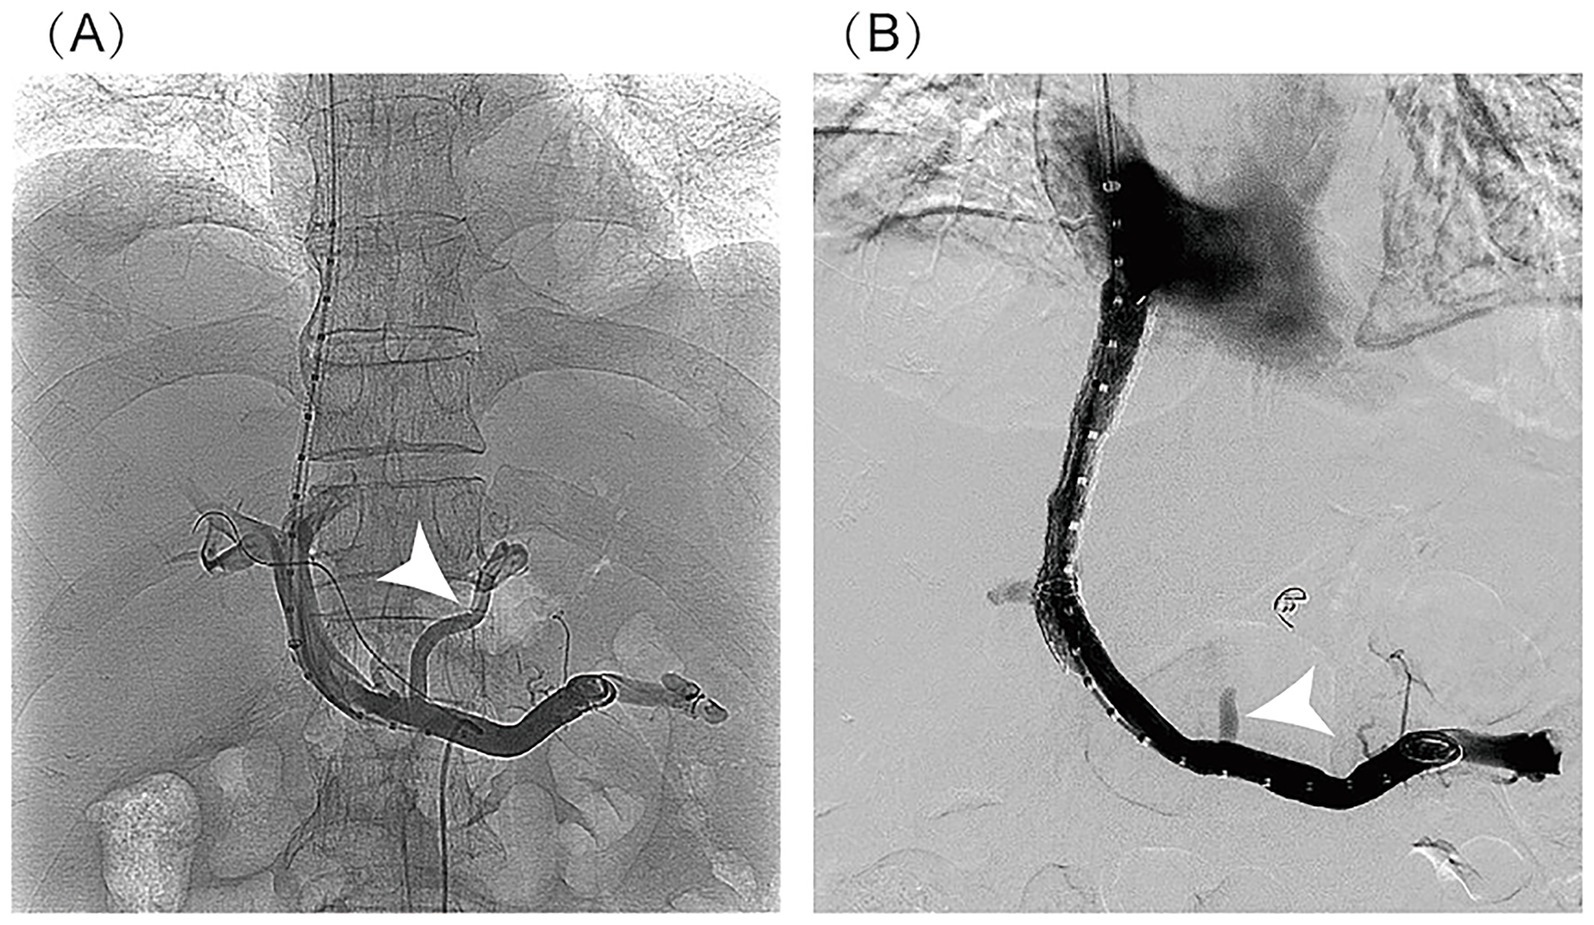

In March 2025, the patient underwent TIPS for refractory ascites with portal hypertension unresponsive to medical therapy (Figure 3). Preoperative portal pressure gradient (PPG) was 23 mmHg. A Viatorr-controlled expandable stent (8–10 mm × 70 + 20 mm) was successfully placed and dilated with a 6-mm balloon in size. Immediate PPG decreased to 7 mmHg. After TIPS, the patient recovered quickly from massive ascites, with stable liver function (total bilirubin: 96 μmol/L). During the 6-month post-procedural follow-up, the patient reported resolution of abdominal distension and recovery of walking ability, with a satisfaction score of 4/5 and significant improvement in quality of life. Additionally, the patient’s liver function showed gradual recovery (total bilirubin: 60.8 μmol/L; albumin 39.2 g/L; INR: 1.28), with the Child–Pugh score improving from class C (11 points) to class A (6 points). The TIPS stent remained patent, and no ascites or overt hepatic encephalopathy was observed (Table 1).

Figure 3

Imaging findings of TIPS procedure: (A) post-puncture portal venography: It clearly demonstrates the normal anatomical course of the main portal vein and its intrahepatic branches, with homogeneous and complete contrast opacification of the portal venous system. No significant luminal stenosis, thrombosis, or contrast extravasation is observed. Portal venous collaterals are visualized (indicated by the white arrow). (B) Post-stent venography: It shows patient blood flow through the stent with a well-defined portal-to-hepatic venous shunt pathway. No contrast stasis or extravasation is noted. Previously visualized collateral vessels have disappeared (indicated by the white arrow). The stent demonstrates optimal morphology, appropriate positioning, and complete expansion.